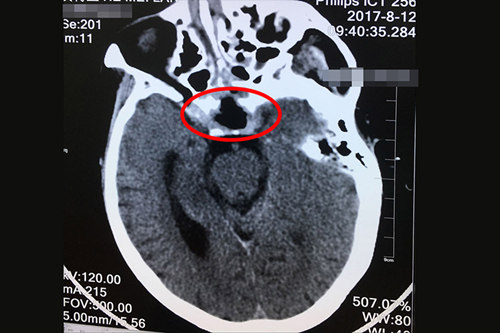

術(shù)后CT顯示:鞍區(qū)垂體大腫瘤切除術(shù)后,大腦半球、小腦及腦干形態(tài)如常。